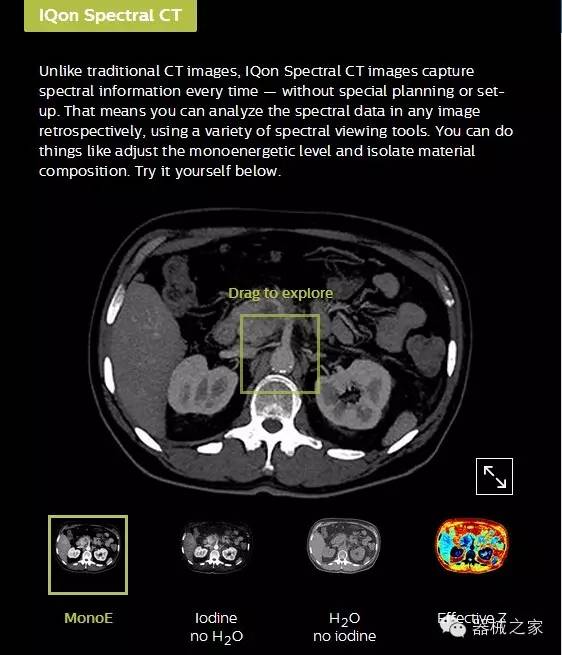

IQon光譜CT能夠按照需求提供光譜量化和工具,并能通過簡單工作流程、在低劑量下對結(jié)構(gòu)進行定性分析

IQon光譜CT -- 是業(yè)界首臺以探測器為成像基礎的光譜CT,它可以在單次常規(guī)掃描下獲得傳統(tǒng)解剖影像及光譜功能影像。不僅可以提供精準的診斷信息,還可簡化工作流程、在低劑量下完成定量與定性分析。